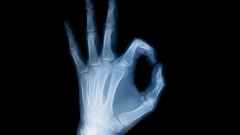

An X-ray, or X-radiation, is a penetrating form of high-energy electromagnetic radiation. Most X-rays have a wavelength ranging from 10 picometers to 10 nanometers, corresponding to frequencies in the range 30 petahertz to 30 exahertz (30×1015 Hz to 30×1018 Hz) and energies in the range 124 eV to 124 keV. X-ray wavelengths are shorter than those of UV rays and typically longer than those of gamma rays. In many languages, X-radiation is referred to as Röntgen radiation, after the German scientist Wilhelm Conrad Röntgen, who discovered it on November 8, 1895. He named it X-radiation to signify an unknown type of radiation. Spellings of X-ray(s) in English include the variants x-ray(s), xray(s), and X ray(s).